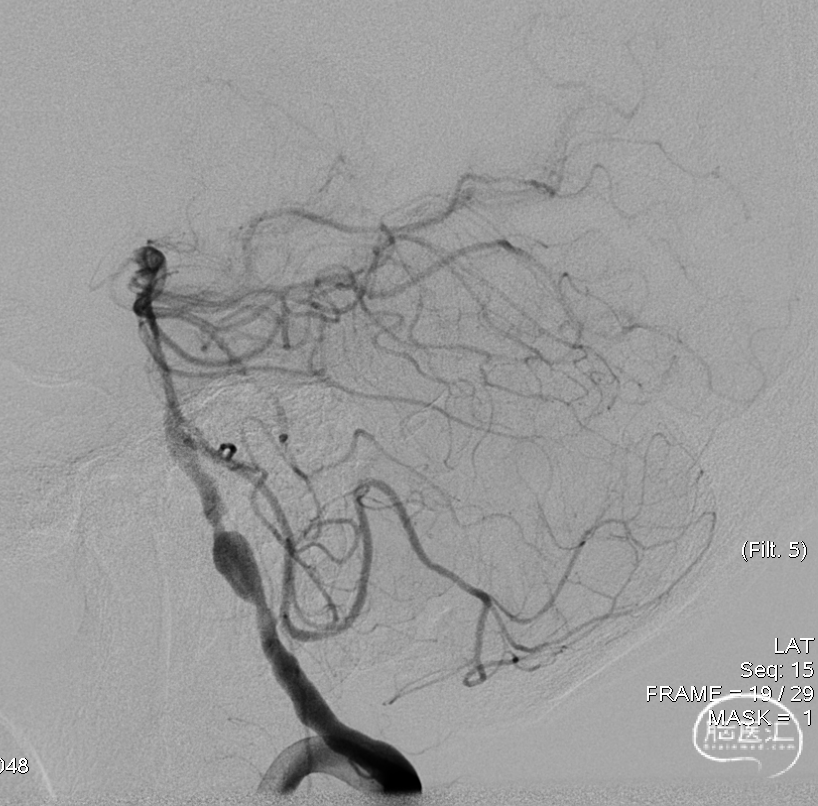

DSA示双侧椎动脉V4段狭窄,右侧为著且合并梭形动脉瘤。

术前DSA。